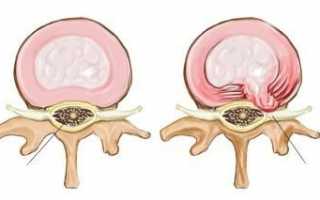

Если говорить о том, что собой представляет любая грыжа в области позвоночника, речь идет о патологии, при которой разрушается фиброзное кольцо с последующим выпячиванием части пульпозного ядра.

Дорзальная грыжа диска является частной формой этого патологического процесса, которая характеризуется смещением пульпозного ядра и выпадением сегмента в область позвоночного канала.

Такие образования считаются гораздо более опасными, ведь в полости позвоночного канала, куда происходит выпадение, находится спинной мозг, его оболочки, сосуды, а также проксимальные отростки нервных корешков. Все это значит, что по мере роста проксимальной грыжи вероятность сдавливания спинномозговых нервов, а также риск осложнений сопутствующего характера повышается в разы.

Наибольшую угрозу представляет дорзальная медиальная грыжа диска – отдельный подвид патологии, при котором выпячивание пульпозного ядра направлено в центр спинного мозга. Помимо этого, выделяют и другие подвиды выпячивания, но о них речь пойдет позже.

В области пятого поясничного и первого крестцового элементов продольная передняя связка укреплена достаточно сильно. Так обеспечивается защита структуры межпозвоночного диска. В связи с этим выпячивание может прорваться в противоположной стороне. Задняя продольная связка отличается меньшей эластичностью. Из-за этого она больше подвержена повреждениям. В результате прорыва образуется дорзальная грыжа диска l5 S1. Выпячивание при этом может быть двух типов. В частности, существует медиальная грыжа диска l5 S1. В этом случае выпячивание случилось в районе серединной линии. Такого рода диагноз специалист ставит, если грыжевое образование проникло в межпозвоночные отверстия. Оно начинает сужаться, а стенки дурального мешка деформируются. Также определяют парамедианную грыжу. В этом случае отмечается искривление столба по типу сколиозного. При этом деформация происходит в другом направлении от выпячивания.